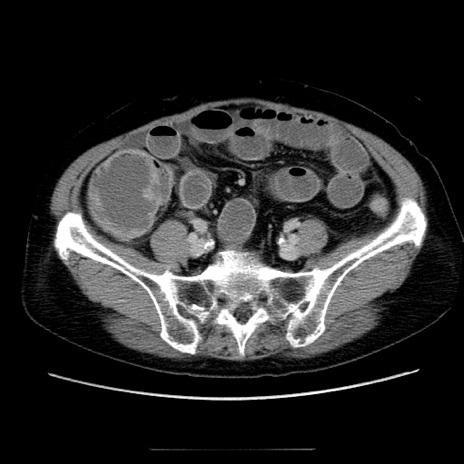

冠状断像

【症例】70歳代女性

【主訴】お腹が張る

【現病歴】1週間くらい前から腹部膨満の自覚あり。昨日夜から増悪したため、本日救急外来受診。

【身体所見】意識清明、BT 36.5℃、BP 165/106mmHg、HR 80bpm、SpO2 98%、腹部:膨満、軟、自発痛・圧痛なし、触診にて不快感あり、腸蠕動音:減弱

【データ】WBC 12600、CRP 1.04